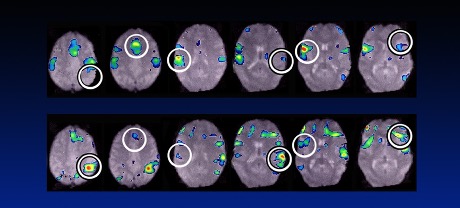

In the slide below, the top image shows my patient’s brain during one of these painful episodes. The bottom row shows the same area of the brain after treatment. The pain she was experiencing after treatment was not as severe. In the brain image figure, the top row represents areas of the brain before treatment. The second and third brain images represent the very bright areas that are associated with pain. Note in the bottom row (after treatment) that the 2nd and 3rd images show much less brightness representing improvement and less pain. In a larger study, we confirmed that the brain scans of abused women show activation in the cingulate cortex that is greater than those without abuse history and this correlated with the degree of pain they experienced.

In other words, the pain is real. It is not all in the patient’s head and it’s not a psychiatric condition. My research shows that there is a physiological and structural change in the brain that causes more severe pain in victims of abuse and trauma. But my research also contains proof of a reason to be hopeful: brain scans of patients taken after treatment prove that these changes are reversible. If you or a loved one is suffering, I encourage you to seek treatment.